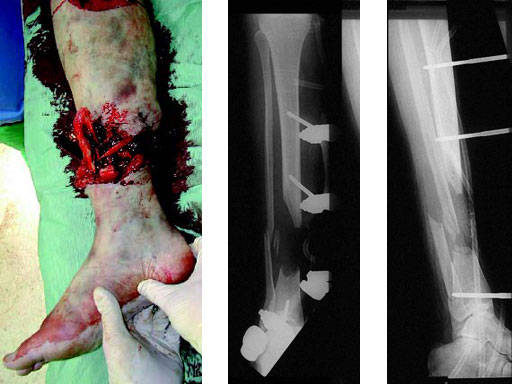

A 33-year-old female sustained a grade III open fracture of the right lower leg.

Case provided by Michael Raschke, Mnster, DE